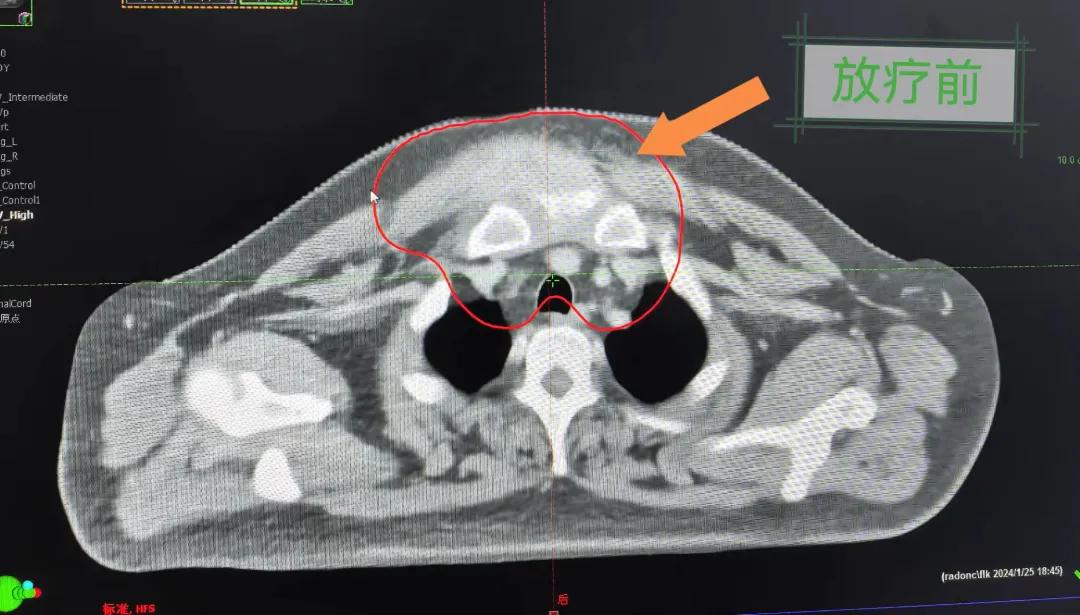

隨后,趙亮主任帶領放療團隊以最快的速度完成了患者的放射治療計劃,在保證放療精準打擊腫瘤的同時,利用先進的三維立體精確放療技術,最大限度的避免心臟、肺部的損傷發(fā)生,整體治療精準度達到1mm以內。經(jīng)過10次的放射治療后,患者疼痛已明顯減輕,胸部腫物肉眼可見的縮小,患者及家屬臉上終于露出久違的笑臉。

治療期間,患者沒有出現(xiàn)明顯不適,治療結束后,患者胸壁腫物由最初8cm縮小至約1cm,后患者至外科行手術治療。